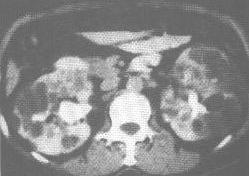

3.CT表现:表现也很典型,肾常显著增大,肾实质内布满多数大小不一的囊伏低密度区,肾盂盏夹于众多囊肿之间,除少数为单侧外,大多为双侧性,诊断容易。多囊肾可并发多囊肝或多囊胰。晚期病例肾实质常显影不良。